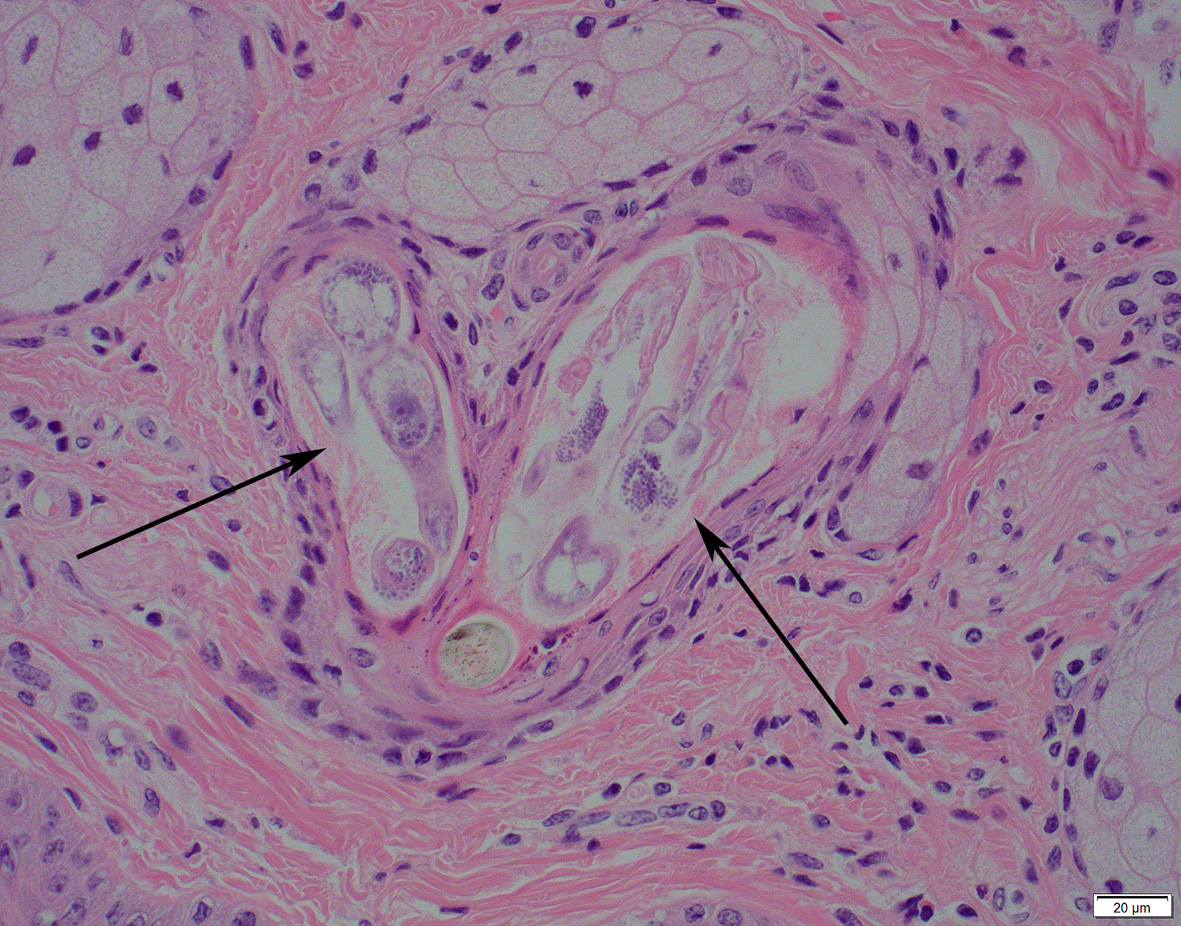

Demodex-mite in hair a follicle. Photo: Marja Kik (DWHC)

Demodex mites are commonly found in many species of animal, including man. There are several sorts of Demodex and these are thought to be species-specific although further information about the different sorts is scarce. Routine investigation into the cause of alopecia typically does not involve determination of the mite to the level of the species. The mites live in hair follicles and reproduce in the sebaceous glands. They can only survive on the surface of the skin long enough to travel between follicles and transmission between animals can occur in this way when there is close contact between individuals so as is seen, for example, between mother and calf.